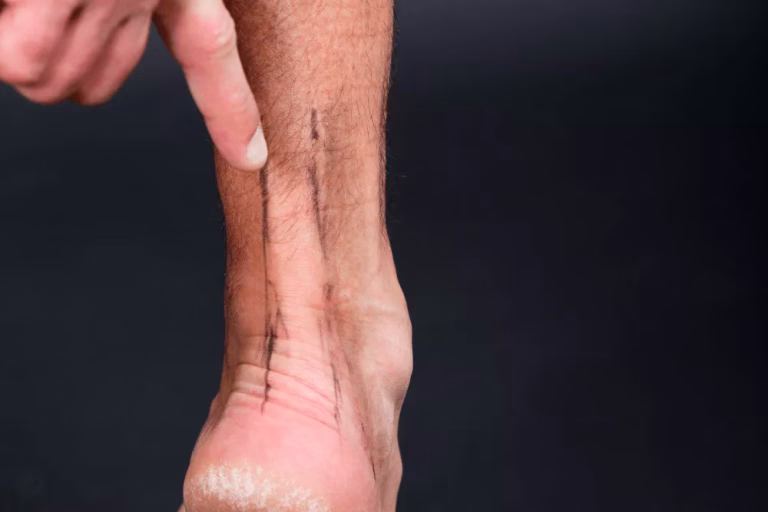

- Tehnici moderne: procedurile artroscopice permit o intervenție minim invazivă, cu recuperare mai rapidă și cicatrici reduse